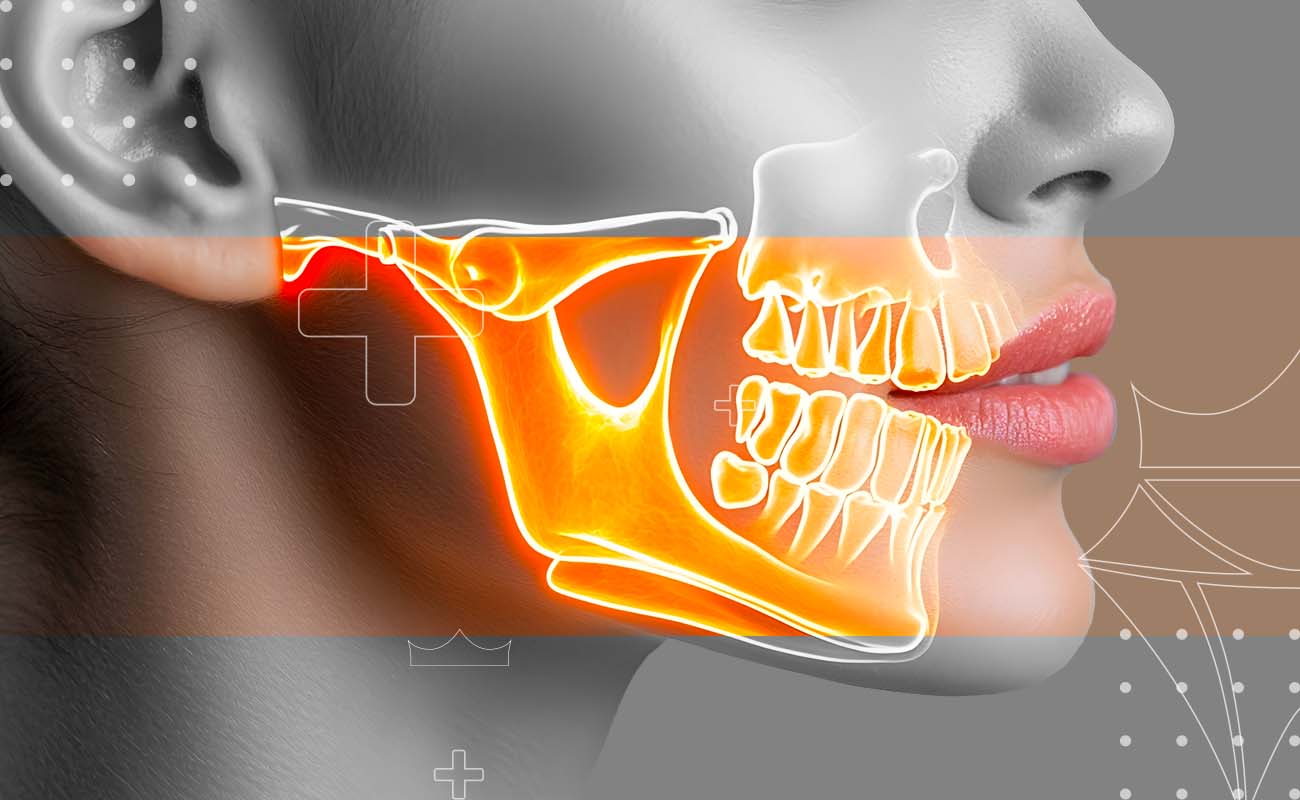

Cysts and tumors in the mouth and jaw can develop for a variety of reasons, many of which are closely linked to dental health and how teeth grow and erupt. These growths are often the body’s response to chronic irritation, infection, or developmental issues.

- A cyst is like a small, fluid-filled sac that can form in your jawbone or the soft tissues of your mouth. These are almost always non-cancerous (benign) and often develop from an infection or as a result of tooth development

- A tumor is a solid mass of tissue. Unlike cysts, a tumor can be either benign (non-cancerous) or malignant (cancerous). While most oral tumors are not harmful, it's essential to have every growth checked by a professional

First, our dentists will perform a thorough examination. We may use modern imaging, such as X-rays or a CT scan, to get a clear picture of the growth. The only way to know for sure what a growth is through a biopsy, where a small sample of tissue is taken and analyzed.